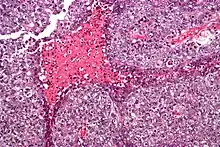

| Micrograph of an embryonal carcinoma showing its typical features – prominent nucleoli, marked nuclear atypia, necrosis, and nuclear overlap. H&E stain. | |

The gross examination usually shows a two to three centimetre pale grey, poorly defined tumour with associated haemorrhage and necrosis.[2]

The microscopic features include: indistinct cell borders, mitoses, a variable architecture (tubulopapillary, glandular, solid, embryoid bodies – ball of cells surrounded by empty space on three sides), nuclear overlap, and necrosis.